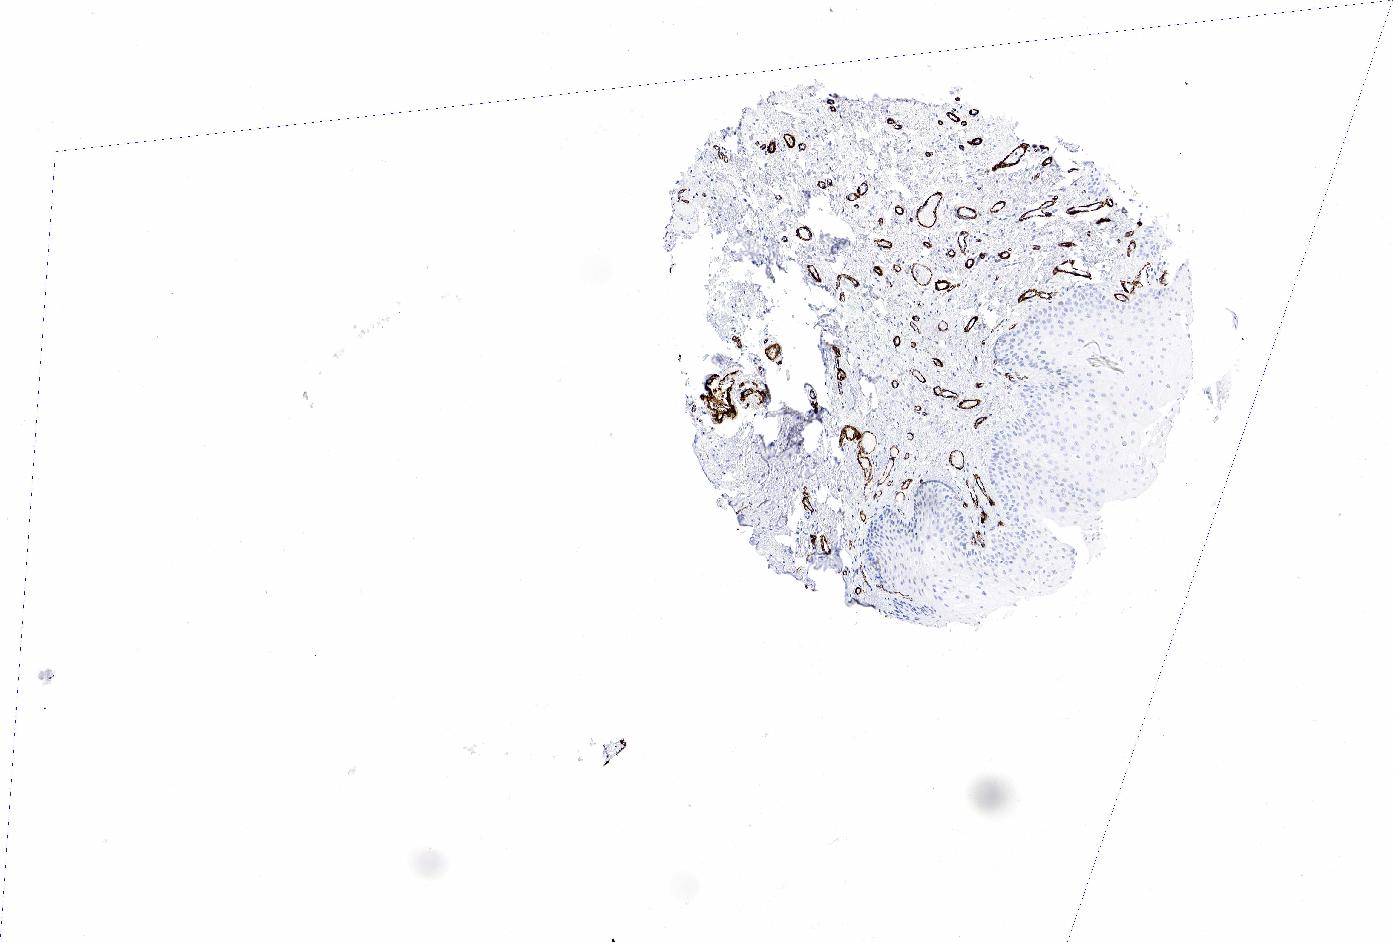

ORAL MUCOSA - Antibody stainingi

Antibody staining in the annotated cell types in the current human tissue is reported as not detected, low, medium, or high, based on conventional immunohistochemistry profiling in selected tissues. This score is based on the combination of the staining intensity and fraction of stained cells.

Each image is clickable and will lead to virtual microscopy that enables deeper exploration of all samples and also displays staining intensity scores, fraction scores and subcellular localization as well as patient and tissue information for each sample.

Antibody HPA041264Antibody HPA041271Antibody CAB000002Antibody CAB003761Antibody CAB013531

Squamous epithelial cells MediumNot detectedNot detectedNot detectedNot detected